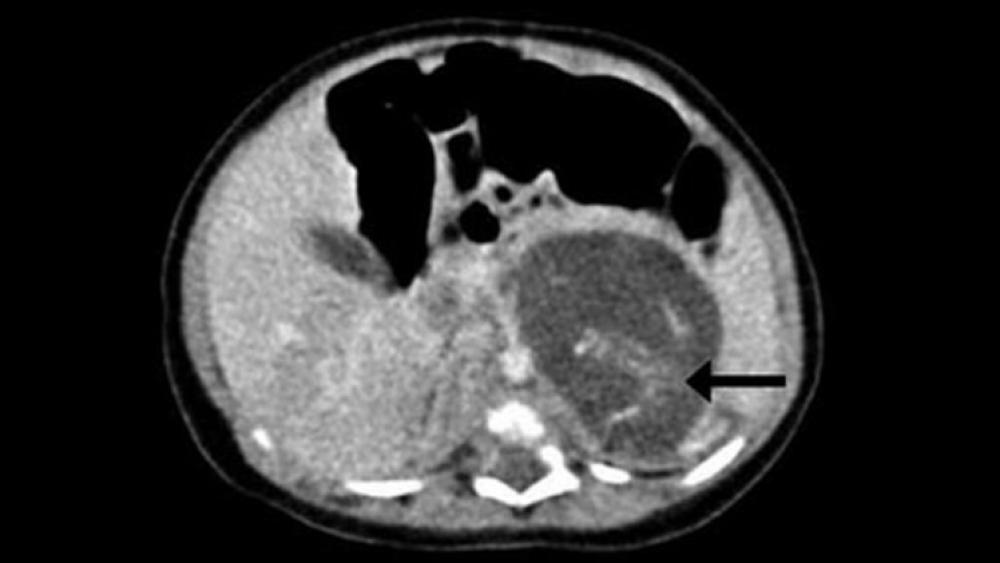

وأظهر تصوير جسم جنين المولودة بالموجات فوق الصوتية الذي أجري قبل ولادتها وجود انتفاخ غريب في منطقة بطنها.

وفي النتيجة أجرى الأطباء عملية لها بعد ثلاثة أسابيع من الولادة، ووجدوا جنينين بين كبدها وكليتها بوزن 9.3 غرام و14.2 غرام، ما يوافق فترتي الحمل لمدة سبعة وتسعة أسابيع.